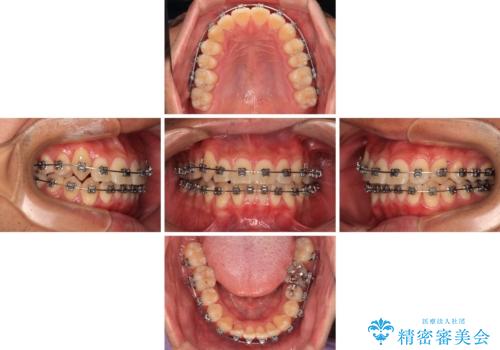

八重歯を無理なくなおしたい ワイヤー装置による非抜歯矯正治療

- 前歯のデコボコと右上の八重歯を気にして来院された患者様です。

マウスピース矯正とワイヤー矯正で悩んでいらっしゃいましたが、非常に強い咬合力であることや、お仕事柄不規則な生活リズムになることが多いとのことで、ワイヤー装置にて矯正治療を行うこととしました。

口元が突出する仕上がりとならないように、舌突出癖改善のトレーニングをしっかりと行っていただきながら、矯正治療を進めていくこととしました。

1年強でワイヤー装置を外すことができ、思ったよりも短期間で終了したため、患者様には大変喜んでいただきました。